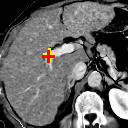

(a)

Refer to caption

(b)

(c) 8.80

(d) 0.9045

(e) 7.80

(f) 0.8999

(g) 9.00

(h) 0.8810

(i) 9.21

(j) 0.8394

(k) 12.79

(l) 0.8265

Figure 7: Example comparison among ADDD + inv (c/d), ADDD (e/f), ADD (g/h), AD (i/j) and D (k/l) networks.